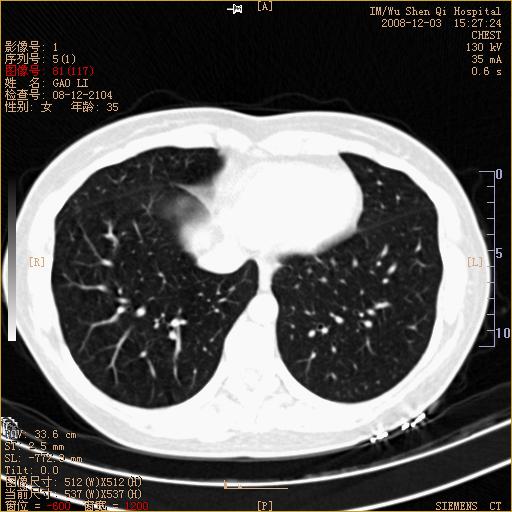

标题: CT16895:女,35岁,反复咳嗽数月,只传部分图像,是否考虑 [打印本页]

标题: CT16895:女,35岁,反复咳嗽数月,只传部分图像,是否考虑

左下肺支扩

典型“印戒征”。

印戒征,支持支扩.

左下肺扩支

印戒征,支扩